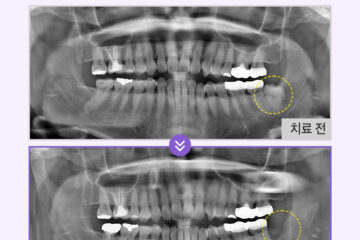

하악 앞니 부분에 생긴 블랙트라이앵글이

너무 도드라져 보여 심미적으로

큰 스트레스를 받고 계셨습니다.

.

정밀 진단 결과 환자분의 하악 전치부 잇몸은

치석 등의 원인으로 인해

이미 상당 부분 아래로 내려간 상태였습니다.

정면에서 보았을 때는 검은 틈이

보이지 않도록 심미성을 회복하되

치아 하단부에는 미세한 통로를 유지하여

환자분께서 스스로 구강 위생 기구를 사용하여

청결을 유지할 수 있도록 했습니다.